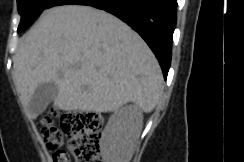

Мультиспиральная компьютерная томография желчного пузыря применяется для оценки состояния стенок желчного пузыря, изучения содержимого его полости, выявления воспалительных изменений, конкрементов и опухолевых новообразований.

В клинике «Доступная медицина» исследование проводится на новейшем 128-срезовом томографе TOSHIBA AQUILION CXL, который позволяет проводить исследование за короткий промежуток времени при сниженной лучевой нагрузке. Посредством инновационных компьютерных программ томограф преобразует полученные данные в 3D-изображения желчного пузыря и желчевыводящих протоков. Это помогает диагностировать заболевания гепатобилиарной системы особенно при нетипичной клинической картине, когда при помощи других методов обследования (УЗИ, МРТ) не удается выявить причину нарушения оттока желчи из желчного пузыря.

МСКТ желчного пузыря в большинстве случаев проводится с применением контрастирования. Пациенту внутривенно вводится рентгеноконтрастное вещество на основе йода. Препарат с током крови попадает в исследуемую область и усиливает контрастность патологических участков, что делает их видимыми на фоне здоровых тканей. При подозрениях на онкологический процесс метод компьютерной томографии с контрастированием помогает обнаружить патологию на раннем этапе развития и провести своевременное лечение.